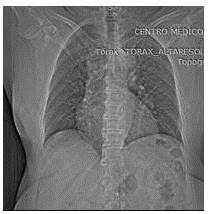

Se trata de paciente femenina de 59 años de edad, con antecedente de terapia supresora a base de anti - TNF y metrotexate debido a artritis reumatoide, quien refiere inicio de su enfermedad actual en marzo de 2010 cuando comienza a presentar tos seca de inicio insidioso, concomitantemente dificultad respiratoria progresiva motivo por el cual acude a centro de salud donde indican tratamiento médico presentando mejoría. La paciente acude a su consulta de reumatología para su control y seguimiento por el uso de la terapia anti-TNF, para su seguimiento se le realiza evaluación médica completa, la cuál incluye examen físico, exámenes de laboratorio y radiografía del tórax (proyección póstero-anterior). La exploración física fue normal y en la radiografía de tórax póstero-anterior, se descubrió una imagen para-cardíaca izquierda a nivel del parénquima pulmonar tipo nodular densa ovalada de borde bien definidos que mide aproximadamente 3,0 cm x 1,7 cm sin calcificaciones u otras anomalías (Figura 1). Se realizó una tomografía computarizada de tórax de alta resolución con contraste intravenoso que reveló una lesión nodular ovalada, homogénea de 26 mm, adyacente al hilio pulmonar izquierdo, borde bien definidos. Resto del parénquima pulmonar sin lesiones focales, estructuras adyacentes conservadas (Figura 2). Debido a los efectos inmunosupresores de la terapia anti-TNF, debe descartarse la posibilidad de infección por mycobacterium tuberculosis (TBC). Se practican exámenes de hemograma, química sanguínea cuyos reportes fueron normales, al igual que las espirometría y la bronco-fibroscopia. El test de la tuberculina PPD, tres baciloscopias y tres citologías de esputo fueron negativas, así como el bronco-aspirado selectivo realizado durante la bronco-fibroscopia y las determinaciones del VIH, Ca 19,9, Ca 125, alfafetoproteína y antígeno carcinoembrionario (CEA).